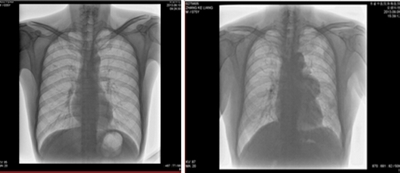

1. 數字化攝影

★適用于全身各部位攝影,包括常規攝影(立位攝影、臥位攝影等,如胸片、頸椎、腰椎、腹部、頭顱、四肢等)和特殊攝影(傾斜攝影、角度攝影等,如瓦氏位、骶髂關節、髕骨軸位、跟骨軸位等)。